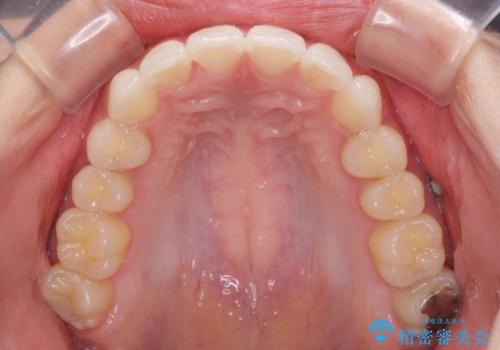

- 前歯2本が飛び出してることを気にして来院された患者様です。

全体的に黄ばんだ歯の色も気になるとのことで、マウスピース矯正により飛び出した前歯を治しつつ、ホームホワイトニングを併用して黄ばみを解消していくこととしました。

歯と歯の間を削ることで、飛び出した前歯が引っ込み、スッキリとした口元となりました。

歯の黄ばみも改善され、明るい歯並びとなりました。